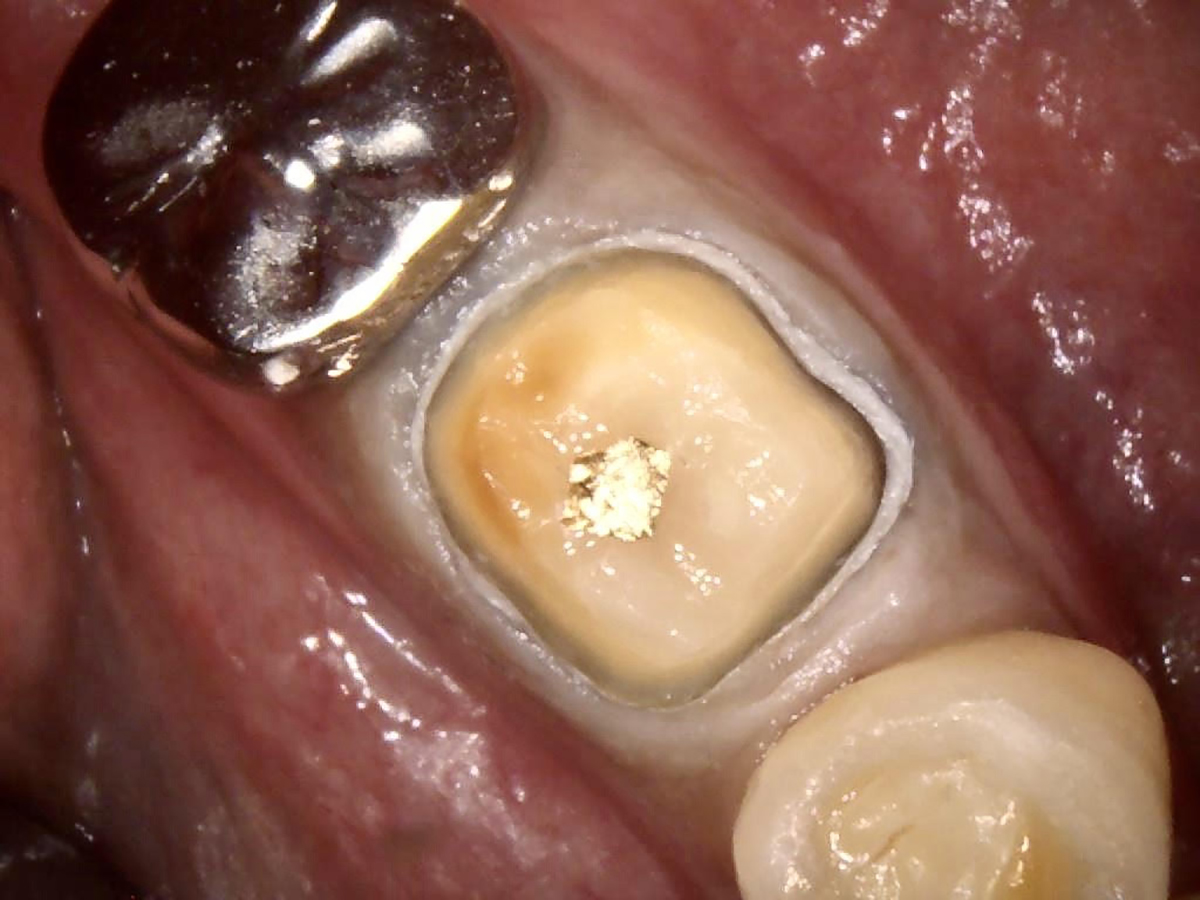

The benefits of universal bonding agents are demonstrated further with the following indirect restoration case example. This restoration was completed in August of 2020. The patient was a 41-year-old man. During the complete examination, it was noted that his lower left first molar (tooth No. 19) was worn and broken with a very deep cavity (Figure 9). The patient described a history of spontaneous pain. The photograph was taken with an intraoral camera. A preoperative periapical x-ray revealed large caries in the pulp chamber. The patient was referred to an endodontist for root canal treatment. After the endodontic treatment was completed, a periapical x-ray was taken before the start of the crown preparation and impression for the laboratory.

Fig 9. Tooth No. 19 was broken and had deep caries.

Figure 9

Fig 10. Universal bond was placed and lightly air-dried.

Figure 10

Fig 11. Tooth with a buildup material and with retraction cords impregnated with epinephrine.

Figure 11